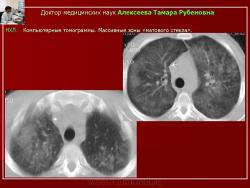

Рис. 8.Б-ной Т. НХЛ.

Компьютерные томограммы. Массивные зоны «матового стекла».

При рентгенологическом исследовании выявлялось понижение прозрачности легочной ткани, диффузное изменение легочного рисунка, выражающееся в его усилении и мелкосетчатой деформации во всех отделах. На этом фоне определялись мелкие очаговоподобные уплотнения. Для уточнения характера обнаруженных изменений больным выполнялось КТ-исследование (рис. 8), которое позволило выявить отек внутридолькового интерстиция, уплотнение интерстиция вокруг бронхиол и мелких бронхов, массивные участки уплотнения легочной ткани по типу «матового стекла», мелкие хаотично расположенные гранулемы с нечеткими контурами.